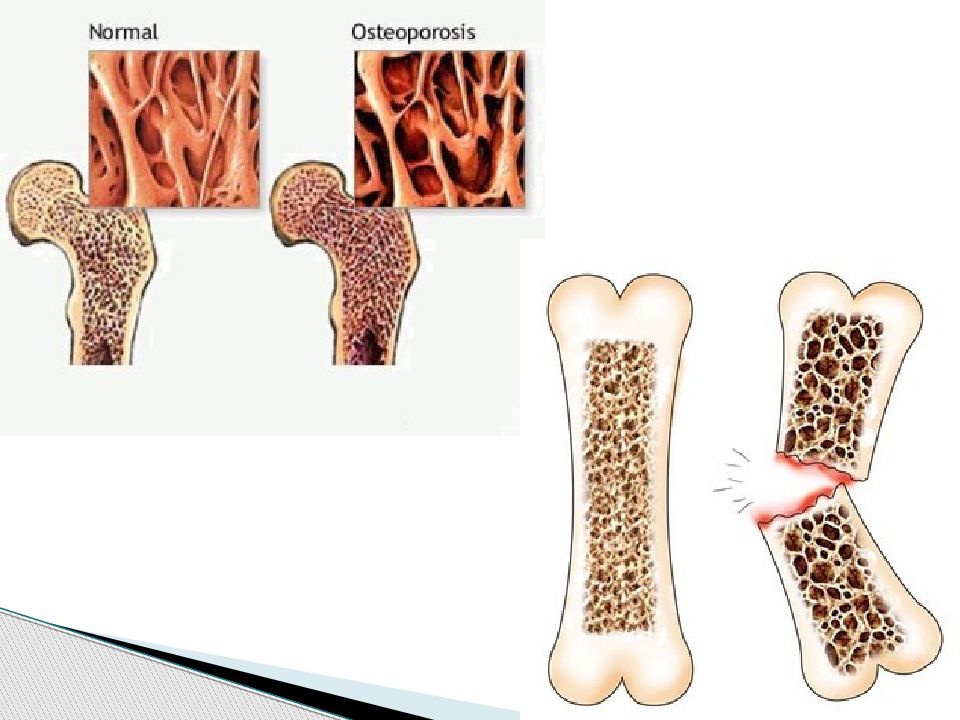

Иллюстрации и снимки, связанные с остеопенией шейки бедра